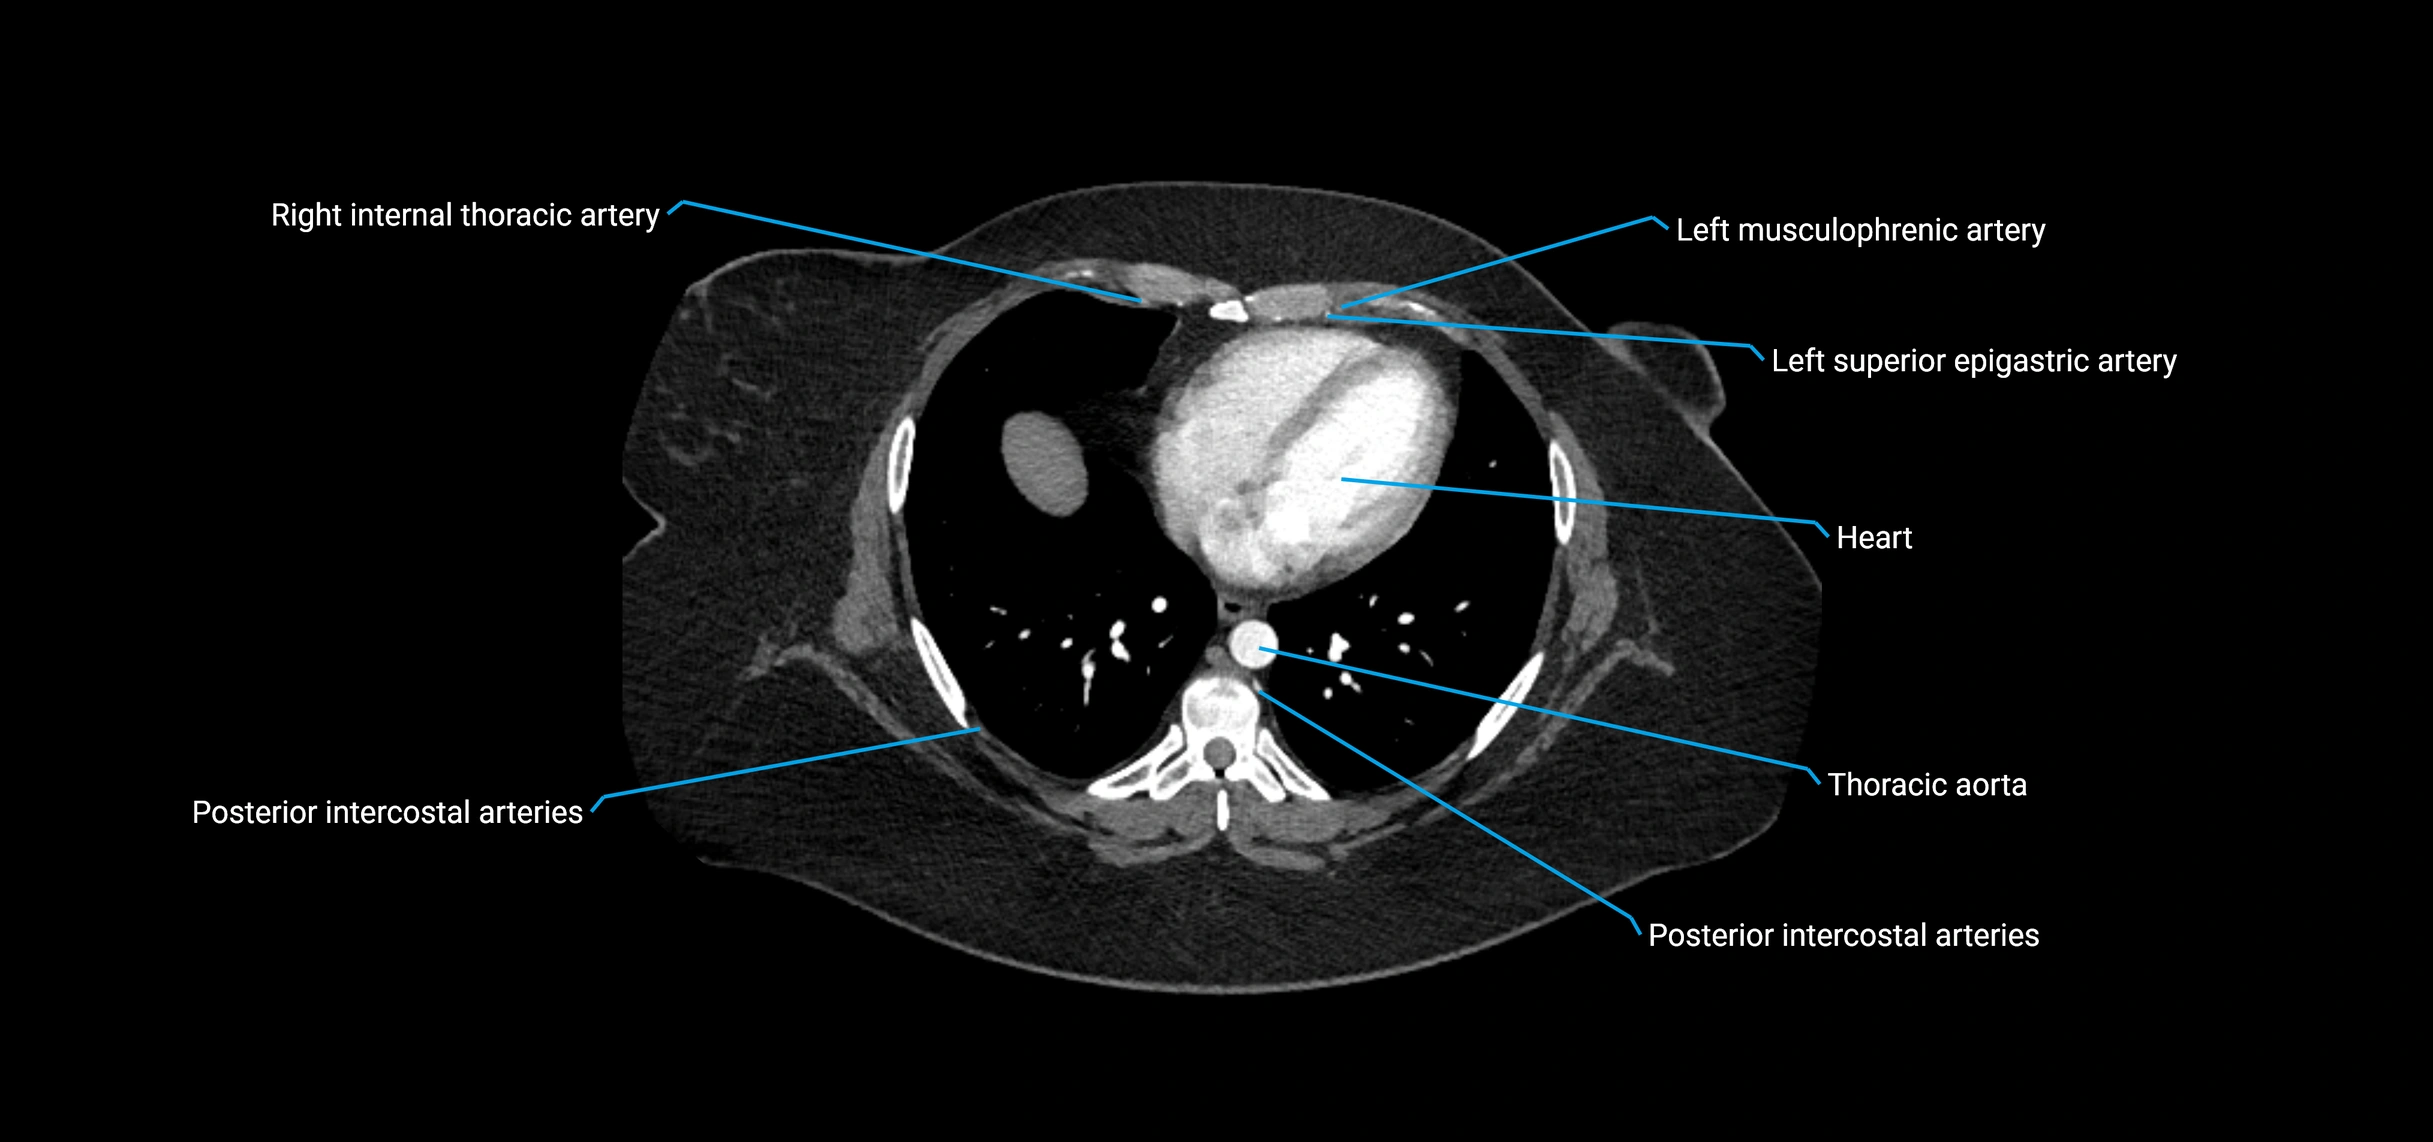

Contrast-enhanced CT (CTA):

• Gold standard for abdominal aortic imaging

• Provides excellent detail of lumen, wall, aneurysm, thrombus, and branch vessels

• Multiplanar and 3D reconstructions help in aneurysm measurement, stent graft planning, and dissection evaluation

• Detects acute rupture, traumatic injury, or occlusion with high sensitivity